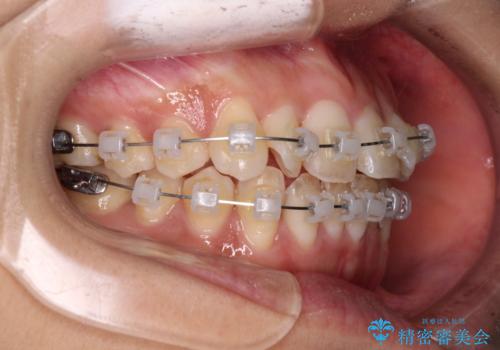

- クリアブラケット

- 1年6ヶ月

- 10-30回

日々前歯の捻れが解消されていくので、歯の動きを楽しみながら矯正治療を進めることができました。